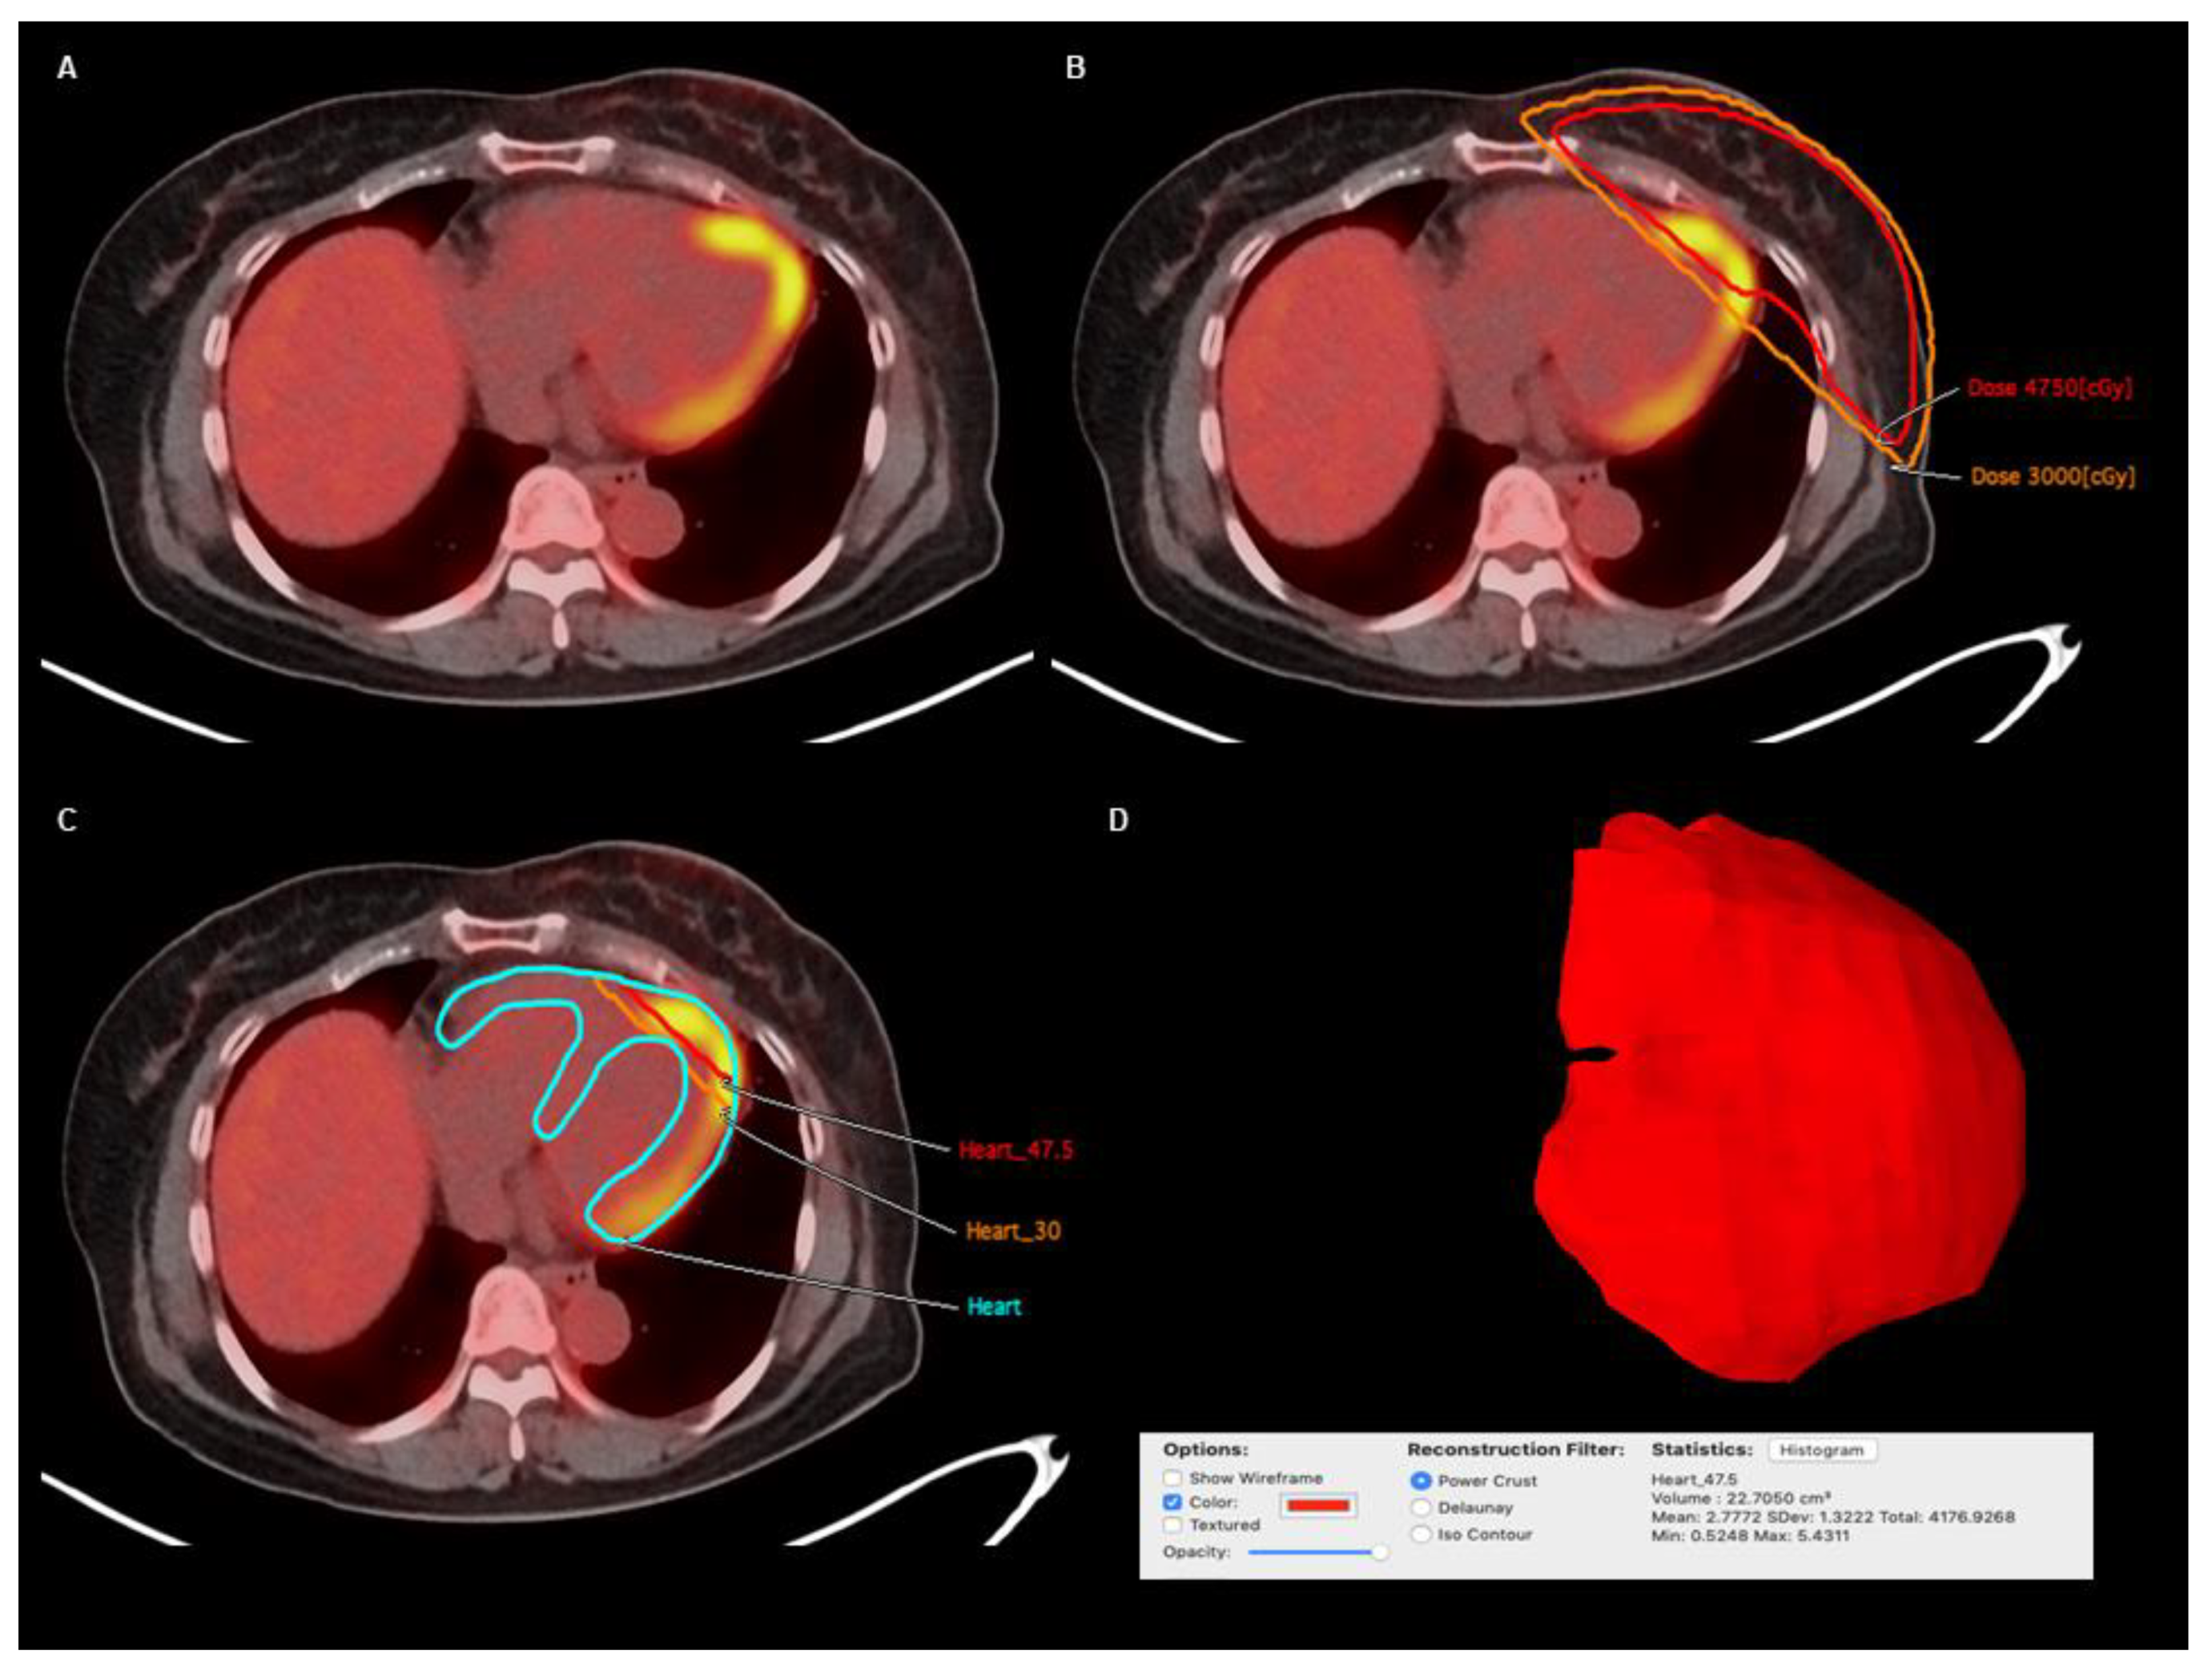

2.5. Image Analysis